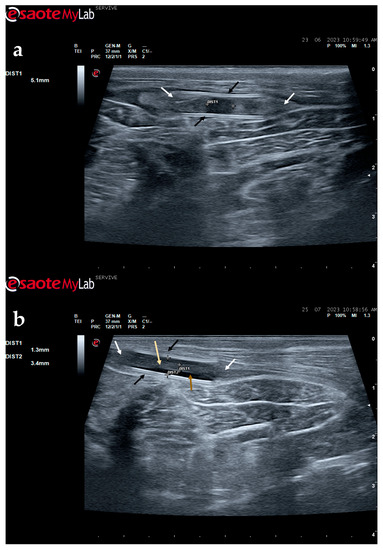

Figure 9.

Ultrasound image of the left peroneal nerve in a sheep subjected to a transection lesion followed by the application of a tube guide. (a) After 1 week, it is possible to observe the tube guide as a hyperechogenic tubular structure (black arrows) at the ends of which the ends of the transected nerve are inserted (white arrows). DIST1 represents the length of the gap left between the two nerve ends. (b) After 3 months, the tube continues to be perfectly visible (black arrows), and the nerve is introduced into its lumen (white arrows); but now, instead of the gap between the nerve tops, an anatomical continuity of the nerve is observed along the entire tubular lumen (beige arrow), indicating a nerve reconnection. In the center of the tubular lumen, a hypoechoic space not filled by nervous tissue is also observed (brown arrow), indicating that the regenerating nerve has not yet occupied all the available space inside the tube guide. DIST1 represents the nerve diameter, and DIST2 represents the inner diameter of the tube guide.

Figure 10.

Ultrasound image of the left peroneal nerve in a sheep subjected to a transection lesion followed by the application of an end-to-end suture. (a) After 1 week, it is possible to observe that the nerve continuity is still interrupted by a gap between the two nerve tops that have not yet fully reconnected (black arrow). DIST1 represents the nerve diameter, which is enlarged and with an increased hyperechogenic appearance due to interstitial edema and inflammatory infiltrate. (b) After 3 months, the nerve already presents an anatomical continuity, it is less hyperechogenic, and its diameter has decreased considerably (DIST1).

The described technique allows an easy follow-up of the progression of nerve regeneration over time after the induction of a lesion in a controlled surgical environment. For example, after the application of a tube guide, in which the nerve tops of a transected nerve are sutured to the ends of the tube, leaving a gap to be filled inside the biomaterial, immediately after surgery, it is possible to identify the tube guide and the nerve tops inside of it by ultrasound (Figure 9). The tube guide appears as a hyperechogenic structure, at the ends of which the nerve tops are observed (Figure 9a), allowing the measurement of the created gap and its evaluation and measurement over time until the total closure and reconnection of the nerve ends (Figure 9b). In the same way, after the application of end-to-end sutures, in which the ends of the transected nerve are coapted and sutured in order to guarantee their reconnection and anatomical continuity, it is possible to observe the nerve continuity (Figure 10), but at early timepoints after the injury, a small hypoechoic gap appears as a result of the transection. An edema, in association with the inflammatory infiltration resulting from the degenerative phase after the nerve injury, promotes a transient increase in the diameter of the nerve (Figure 10a) that ends up disappearing over time (Figure 10b). In addition to the increase in diameter, due to interstitial edema, the nerve also appears with an increased hyperechogenic appearance. The main advantage of applying ultrasound in the monitoring of nerve regeneration will be to allow the observation of macroscopic morphological changes in the nerve over time, namely changes in its anatomical continuity, in the dimensions of the created nerve gaps, in their diameter, and in the presence or absence of edema and inflammatory infiltrate. Microscopic changes such as endoneurial microvascular degeneration, demyelination/remyelination, and axonal density and reorganization should be later confirmed by more sensitive histomorphometric techniques such as nerve stereology. At the same time, the functional translation of the regenerative process can be evaluated in parallel through functional and behavioral tests, determination of nervous conductivity, and biomechanical and kinematic gait studies.